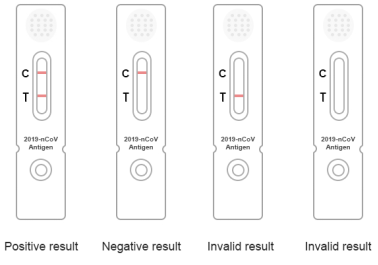

Test card analysis (as shown in Figure 5):

1. Invalid result: the quality management line (line C) does not respond, the line is invalid, and it needs to be retested.

2. Negative results: quality management line (line C), red ribbon, coloring.

3. Culture results: the two red bands of test line (t line) and quality management line (C line) are colored.

Figure 5 Interpretation of test results